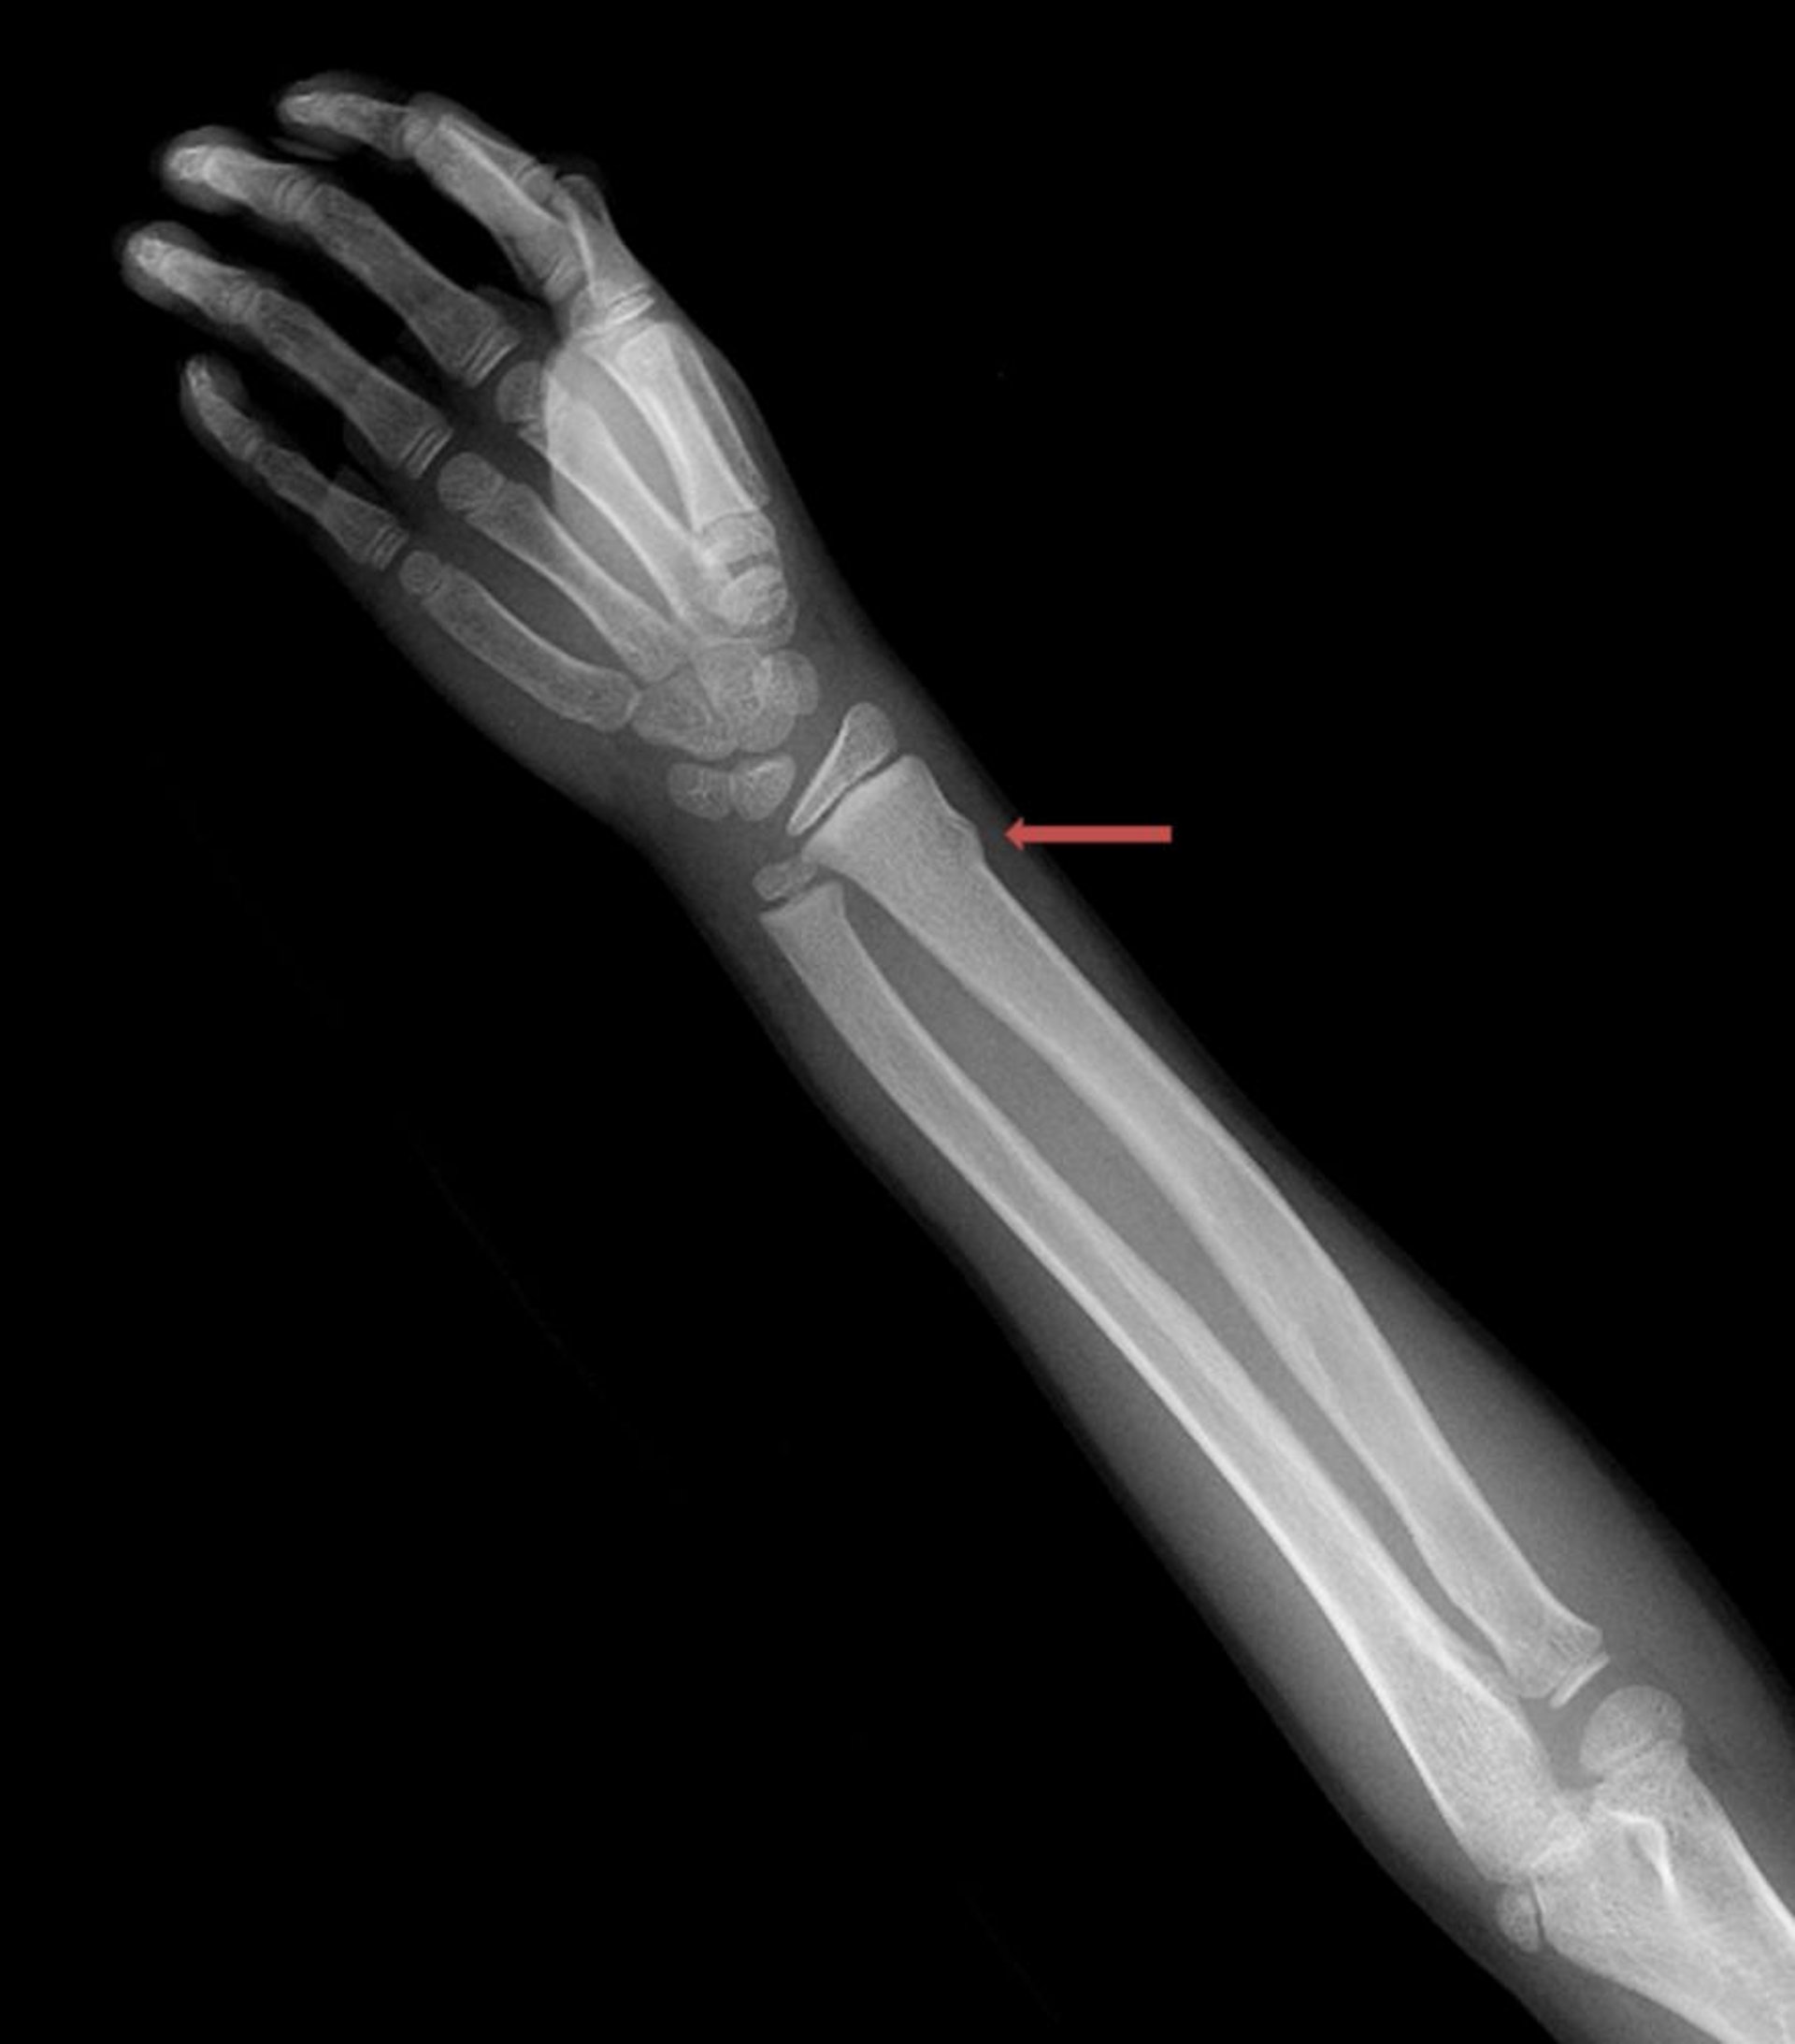

Fracture du poignet en motte de beurre

Cette fracture en tore du radius distal n'est visible que comme une légère irrégularité de la corticale osseuse.